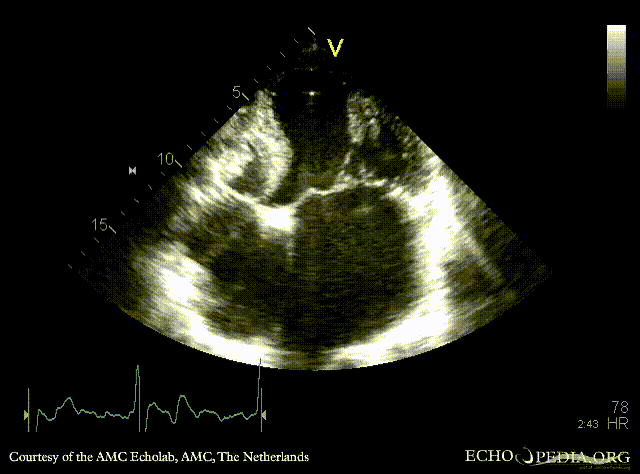

| Courtesy of: AMC Echolab, AMC, The Netherlands | |

| A4CH | |